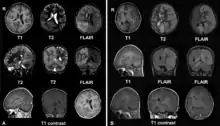

Left: December 2008, the patient was presented with headache and epilepsia partialis continua. There are lesions with local brain swelling in the right parietal and occipital lobes and right cerebellar hemisphere.

Right: April 2009, the same patient, now she is comatose with epilepsia partialis continua. There is progression of the encephalitis - the left cerebral hemisphere has been involved with severe brain swelling and shift of the midline structures.

The diagnosis may be made on the clinical features alone, along with tests to rule out other possible causes. An EEG will usually show the electrical features of epilepsy and slowing of brain activity in the affected hemisphere, and MRI brain scans will show gradual shrinkage of the affected hemisphere with signs of inflammation or scarring.[9]